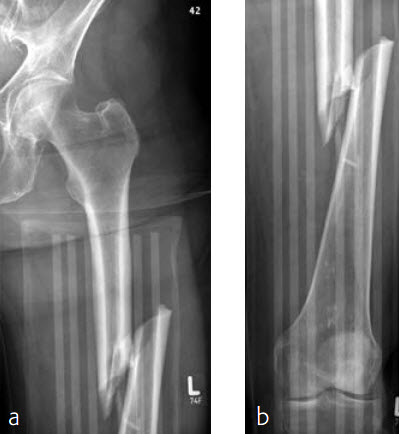

Case 1: Subtrochanteric femur fracture

An 86-year-old patient fell at home while dressing, sustaining a subtrochanteric left femur fracture (Fig 1). The CT scan confirmed no involvement of the intertrochanteric region or the piriformis fossa. Fixation was with FRNA for piriformis fossa entry point in reconstruction locking mode and transverse locking (Fig 2).